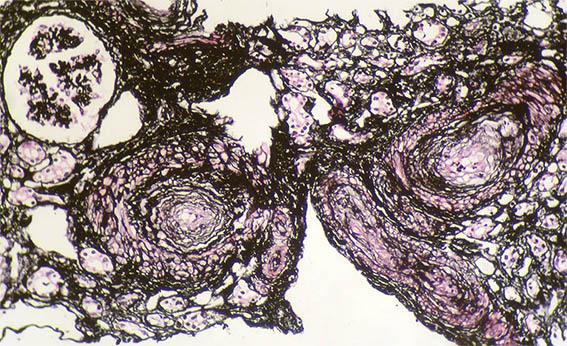

Figure 5. Methenamine-silver stain, X400.

Figure 6. Methenamine-silver stain, X400.

Figure 7. Methenamine-silver stain, X400. Mesangiolysis.

Figure 8. Methenamine-silver stain, X100.